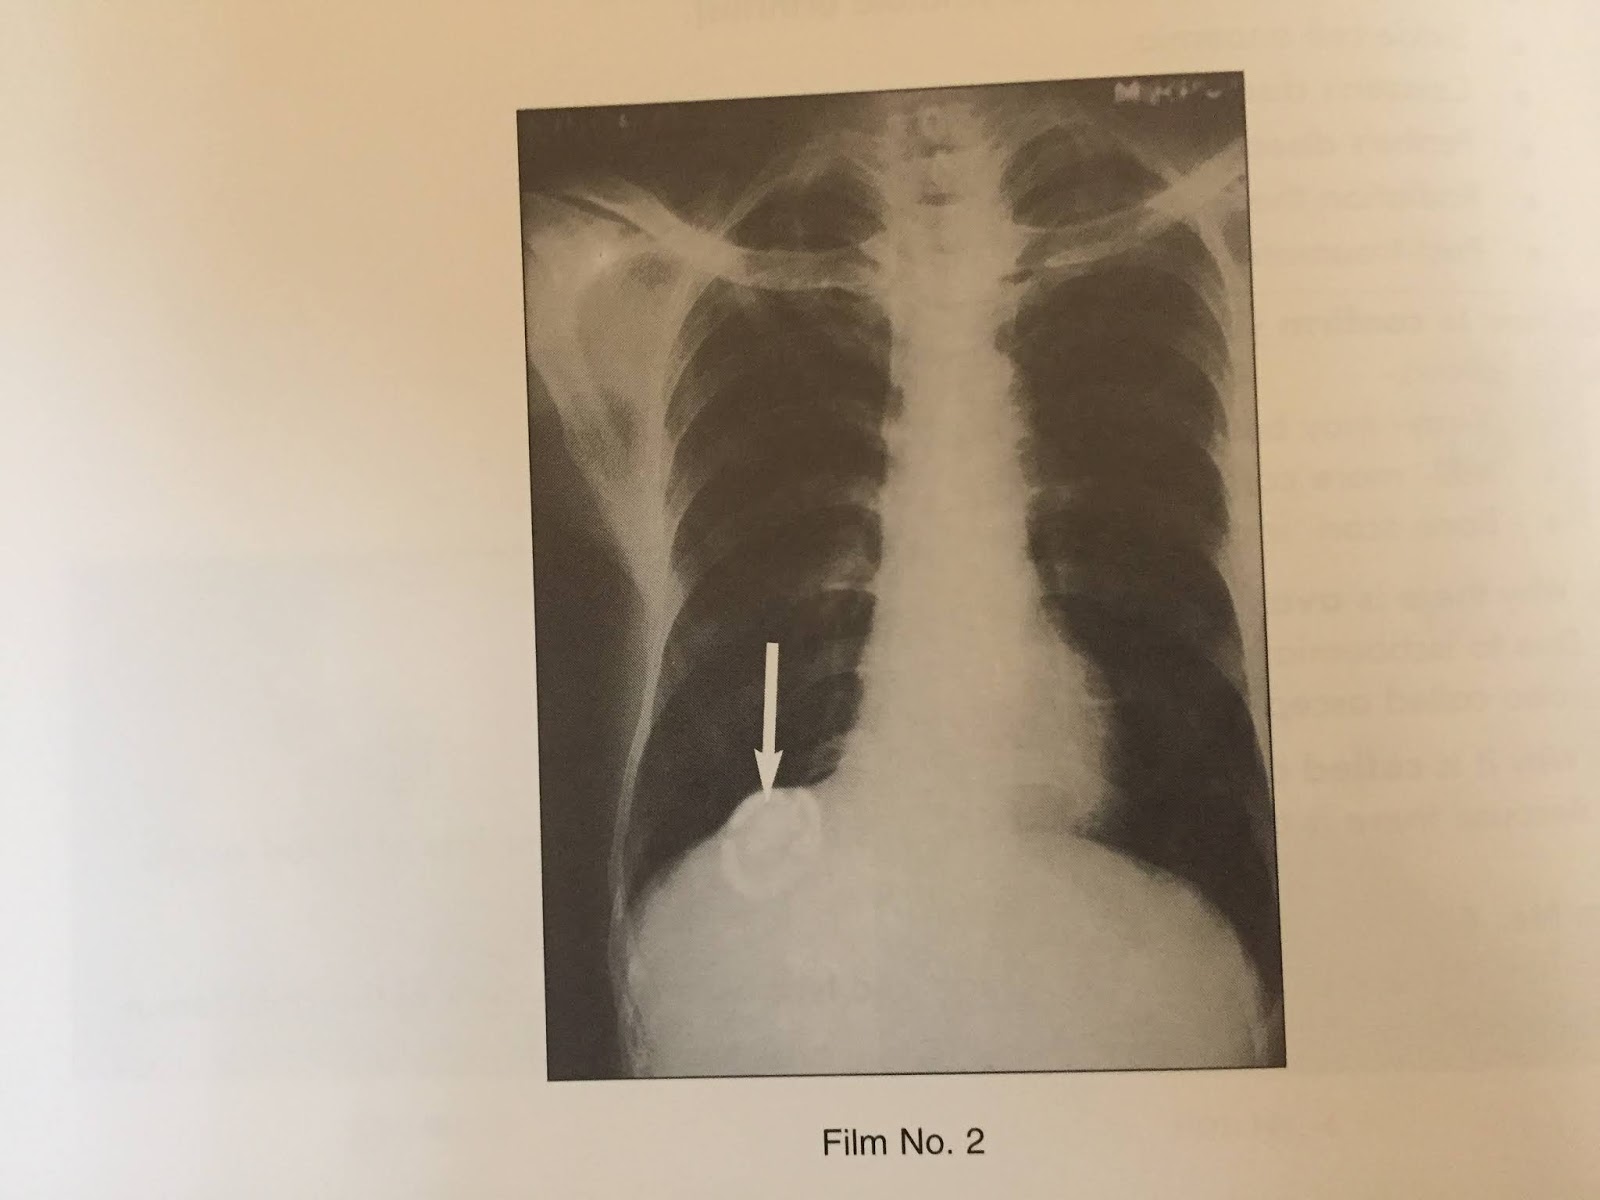

From medicalschoolimportant.blogspot.com

XRAYS HYDATID CYST OF THE LIVER Bad Liver X Ray a liver scan may give doctors valuable information about the health and function of the liver. Assessment of liver size is commonly made on ultrasound or ct, although gross. common signs of liver damage include: ct scans of the liver are useful in the diagnosis of specific types of jaundice (yellowing of the skin and eyes as. Bad Liver X Ray.

XRAYS HYDATID CYST OF THE LIVER Bad Liver X Ray But early treatment may give the liver time to heal. a liver scan may give doctors valuable information about the health and function of the liver. It may also help with. common signs of liver damage include: This can be caused by conditions such as chronic hepatitis,. ct scans of the liver are useful in the diagnosis. Bad Liver X Ray.